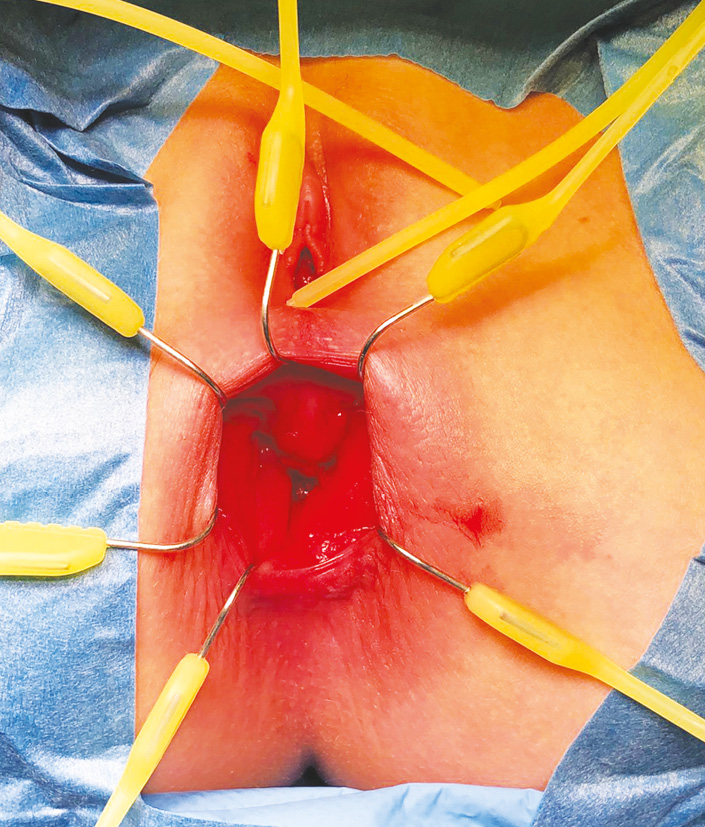

- МРТ малого таза (рис. 1): стенка прямой кишки расслоена, просвет ампулы сужен за счет крупного дополнительного, очевидно, подслизистого, образования, выступающего в просвет кишки, бобовидной формы, размерами 22×33×45 мм, в нижних отделах с неровными краями. Параректальная клетчатка гипертрофирована. Ретроректально увеличенный лимфоузел 6 мм. Заключение: геморрагически-воспалительный субстрат? Геморрагически-некротическое новообразование/полип?

Рис. 1. Магнитно-резонансная томограмма. Фронтальный (а) и поперечный (b) срезы. Визуализируется образование прямой кишки, суживающее просвет (указано стрелкой).

Fig. 1. Magnetic resonance imaging. Frontal (a) and transverse (b) sections showing a rectal mass narrowing the lumen (indicated by an arrow).